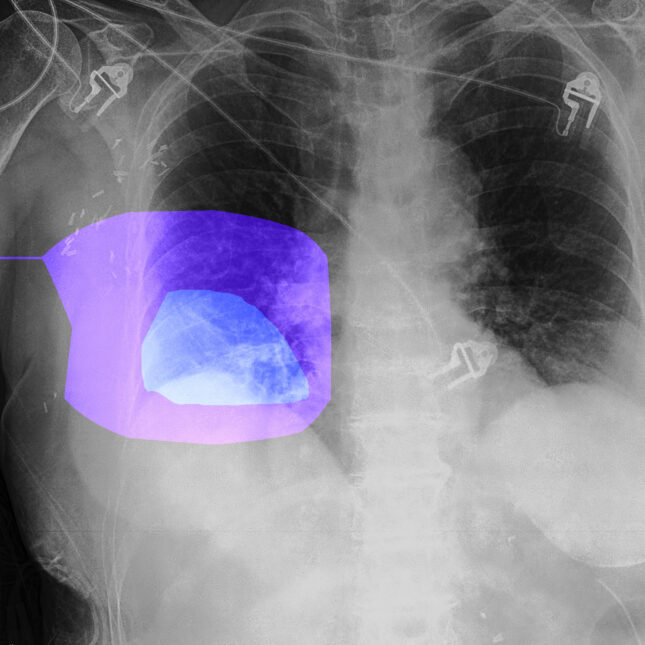

Harnessing Multimodal Capabilities for a Holistic Patient View

Modern healthcare is inherently multimodal. A patient’s story is told through text (doctor’s notes), numbers (lab values), and images (X-rays, CT scans, pathology slides). The advent of models that can process and reason across these different data types is a game-changer. As highlighted in GPT Multimodal News, models like GPT-4o can analyze a radiologist’s written report in conjunction with the actual medical image, or correlate structured lab data with a physician’s narrative assessment. This ability, often discussed in GPT Vision News, allows the AI to form a much more comprehensive and nuanced understanding of the patient’s condition than a text-only model could. As we look toward future GPT-5 News, we can anticipate even tighter integration of these modalities, enabling AI assistants to spot subtle correlations that might be missed by a human reviewer working under pressure.